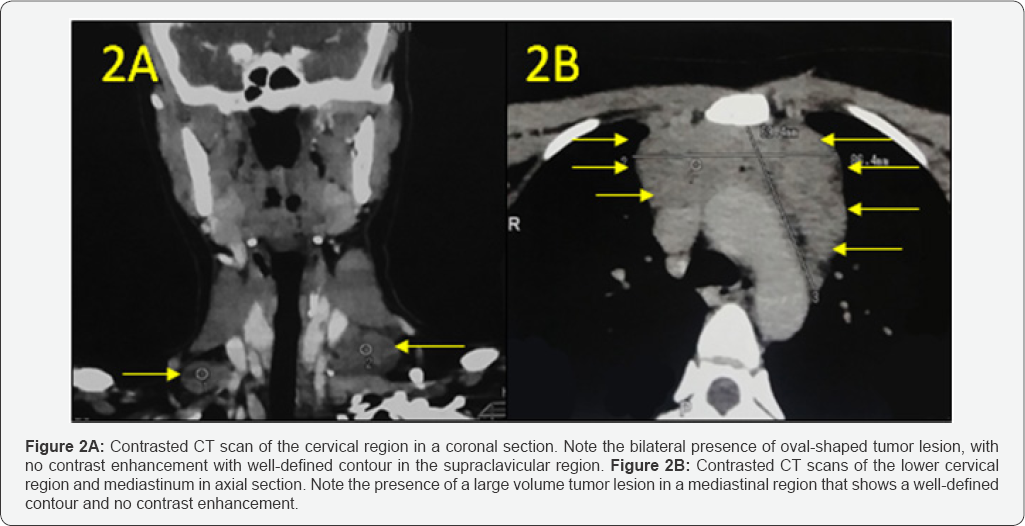

Contrast computed tomography of the left cervical region revealed the presence of multiple lymph nodes in the pre-aortic anterior mediastinum and in the cervical chain IV, VA and VB bilaterally. The lesions showed no contrast enhancement and presented well defined contour (Figure 2A & 2B).